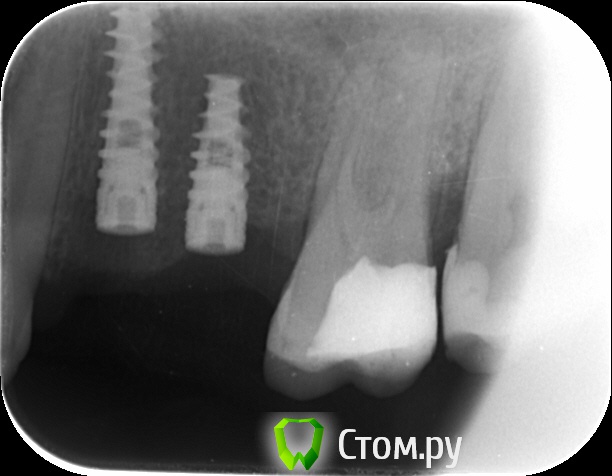

an_ver Опубликовано 12 сентября, 2014 Автор Поделиться Опубликовано 12 сентября, 2014 Вот снимки Ссылка на комментарий

an_ver Опубликовано 12 сентября, 2014 Автор Поделиться Опубликовано 12 сентября, 2014 На момент установки Ссылка на комментарий

k.t.m. Опубликовано 12 сентября, 2014 Поделиться Опубликовано 12 сентября, 2014 длина имплантата 6мм или ракурс такой? Ссылка на комментарий

an_ver Опубликовано 12 сентября, 2014 Автор Поделиться Опубликовано 12 сентября, 2014 (изменено) длина имплантата 6мм или ракурс такой?Не, 8 мм.У Альфы на станд.платформе нет 6 мм,только на широкой Изменено 12 сентября, 2014 пользователем an_ver Ссылка на комментарий